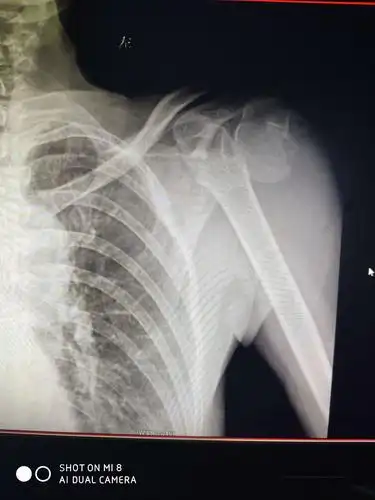

其它 浅色的夏末的美篇 写美篇患者余某,铁门镇人,以"左肱骨头粉碎性